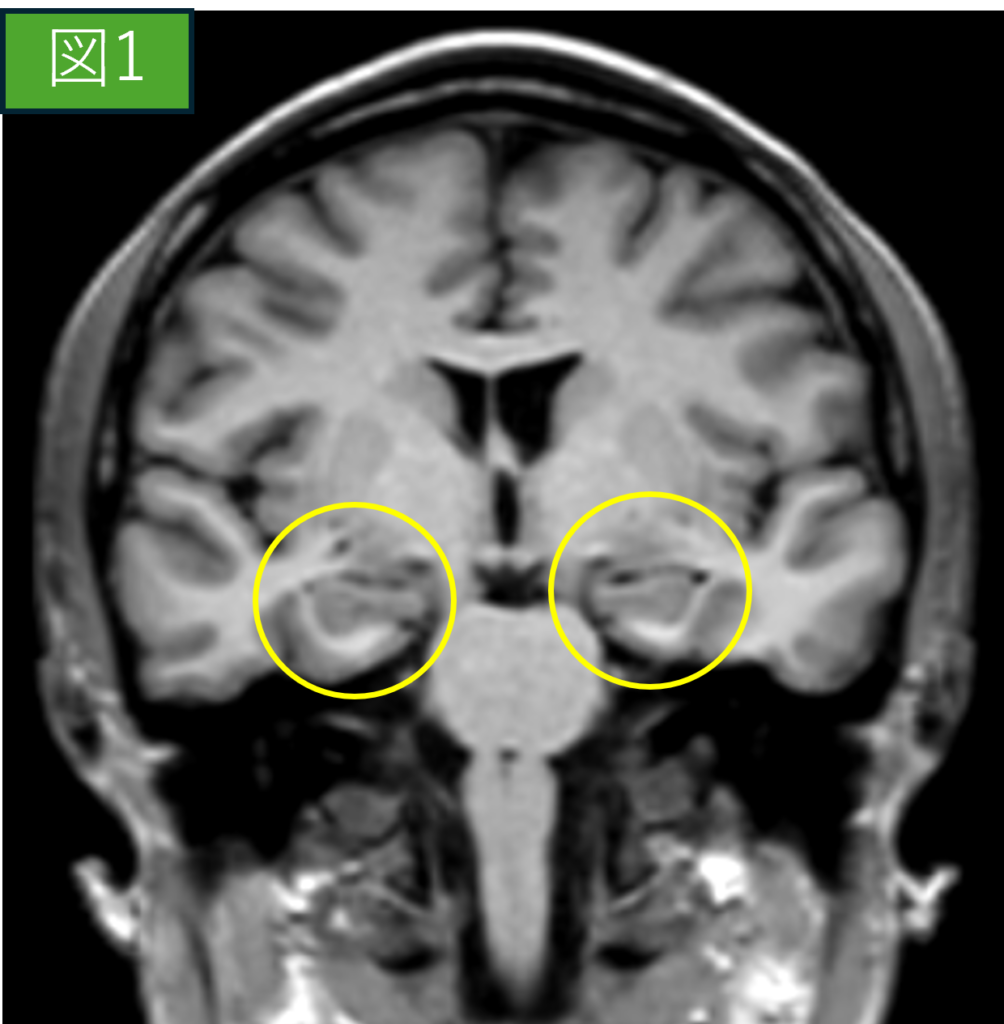

正常MRI画像(冠状断像)

症例画像から図1(正常画像)・図2(脳萎縮画像)

〇内が海馬を示しています。

正常の海馬は成人であれば6cm程の大きさであり、加齢や生活習慣によってはさらに小さくなります。図1と図2を比較すると脳全体の萎縮や海馬の萎縮も顕著に見られた症例です。